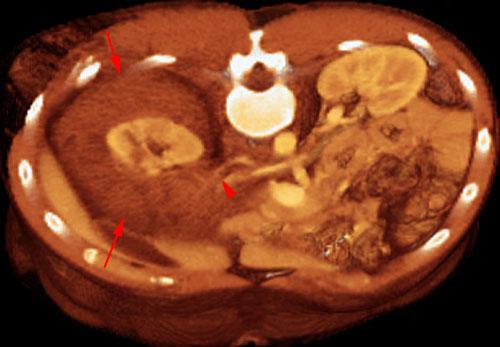

Estallido renal

VR seccional. Visión axial cenital. AngioTC de aorta abdominal mostrando un afectación del pedículo vascular (punta de flecha). Gran hematoma perirrenal (flechas)